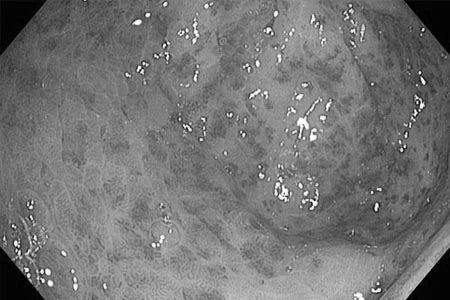

- Фиброгастроскопия. Ця діагностична процедура необхідна для оцінки стану слизової шлунка шляхом введення через рот гнучкою оптоволоконної трубки з камерою. У процесі цієї процедури визначається ступінь ураження слизової і наявність внутрішніх кровотеч. Також проводиться дослідження секреторної активності шлунка, вивчається склад шлункового соку.